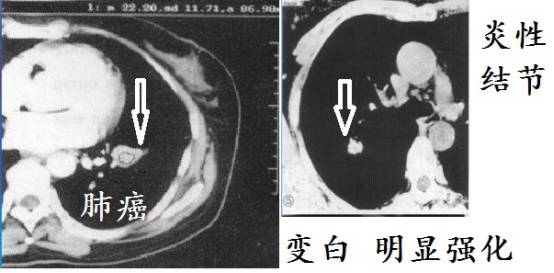

少增强

肺结核因为干酪性坏死,增强CT强化一般不明显!但是,有些肺结核在增殖阶段,生长活跃,没有形成明显坏死,有可能显著增强。这个要综合考虑。但是大多数肺结核增强一般不会显著强化。肺癌生长需要血供,常常显著强化。

■ 无强化:强化CT值<10 Hu;轻度强化:强化CT值达10 ~20 Hu;中度强化:强化CT值达20~30 Hu;重度强化:强化CT值>=30 Hu。

■ 也有学者这样分类:轻度强化:CT值上升<20 HU;中度强化(CT值上升20~40 HU),明显强化(CT值上升>40 HU)。

简单的说,就是增强CT上,病灶越白,强化也明显,肿瘤、一般细菌感染引起炎性结节常常明显强化,肺结核强化不明显。

上图是肺结核增强CT,病灶几乎无强化,和下面差别很大。